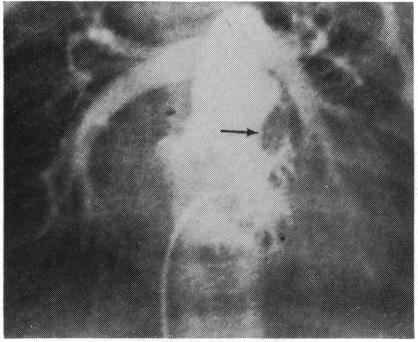

Congenital heart disease--changes in form and function.

Br Heart J. 1979 Jan;41(1):1-22. doi: 10.1136/hrt.41.1.1.